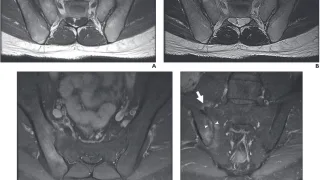

手術日+728日目 2026/2/25(水)(筋肉内神経鞘腫)

午前の病院での仕事今朝は, 雨.いよいよ, 雪解けの季節になってしまいました.気温は, 6 ℃.少雨だった地域には, 惠の雨ですが, スキーヤーにとっては, ありがたくないです.最高気温が低い予報なのが, せめてもの救いです.8時前に病棟に...